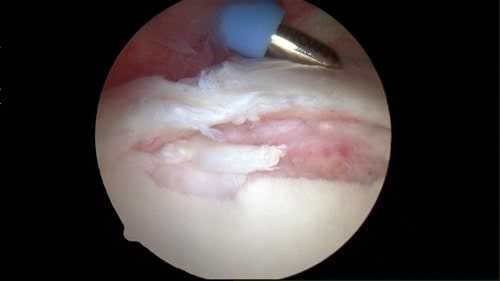

На рис. Инструмент находится на суставной губе, которая, как видно, оторвана от суставной впадины.

На рис. Суставная губа фиксирована швами.